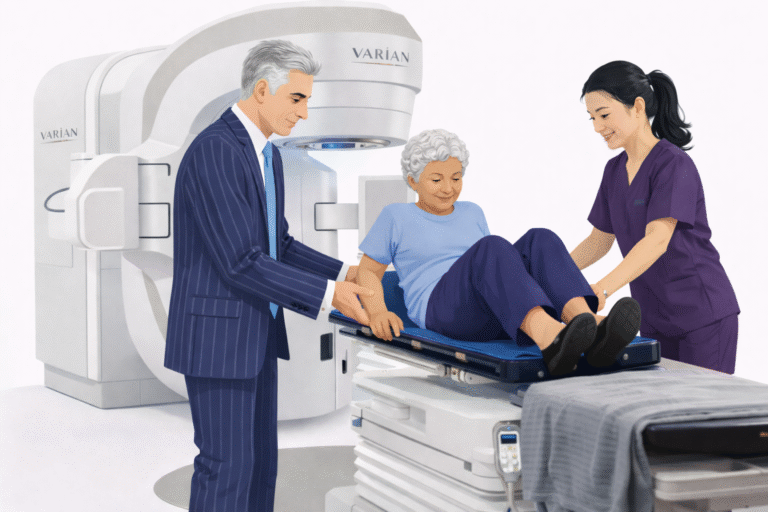

How Pinpoint Radiotherapy Can Help

At Pinpoint Radiotherapy, we specialise in delivering precise, advanced treatments like Stereotactic Radiosurgery for brain metastases. Our expert team uses the latest technology to tailor each patient’s treatment plan, ensuring that radiation is delivered with the utmost precision. We understand that every patient’s journey is unique, and we are committed to providing compassionate care that focuses on both the quality of life and effective disease management.

If you or a loved one is facing brain metastases and considering treatment options, contact Pinpoint Radiotherapy to learn more about how SRS can be part of your care plan. We’re here to support you with advanced, patient-centred care every step of the way.